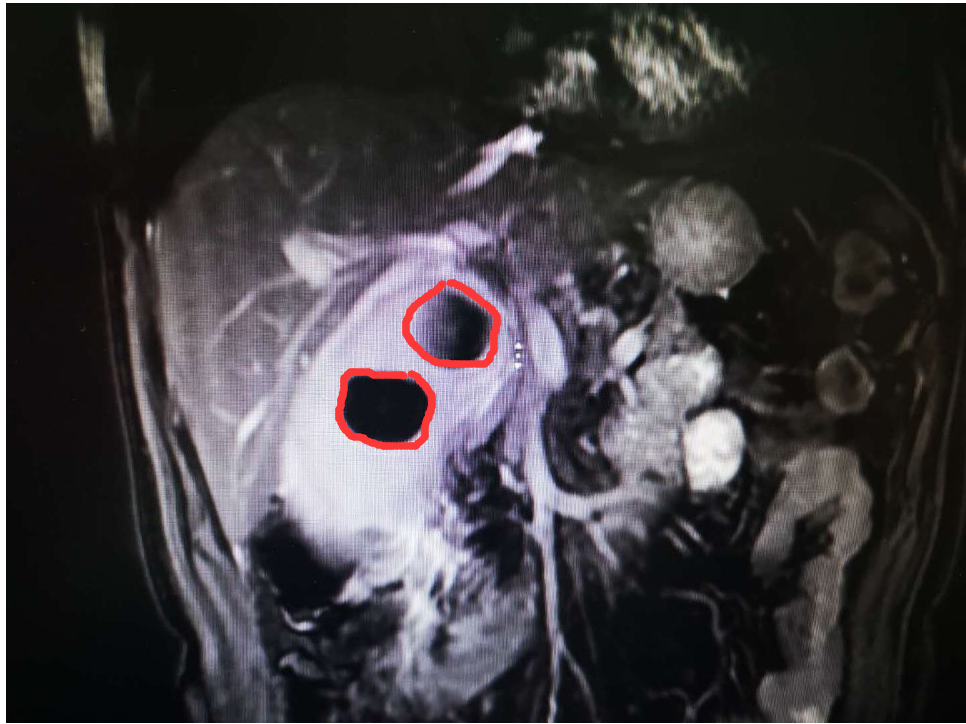

(胆结石的影像)

2月12日下午3时,医院东院外一科主任佘浩清,副主任龙在峰,主治医师张旌,医师王映为其进行微创手术。手术中,发现杨先生的胆囊被结石撑大了3倍以上,胆囊壁也有一厘米左右厚(正常约3毫米厚),胆囊炎症、水肿与周围组织粘连严重。“我们通过腹腔镜为其进行手术,在腹部打两个1厘米大小和一个1.5厘米大小的小孔进行操作。手术难度大,风险也很高,但我们迎难而上。经过大家的努力,顺利切除了肿大的胆囊,放置腹腔引流管,并取出了4颗胆结石,每个都有两三公分大小。”佘浩清表示。